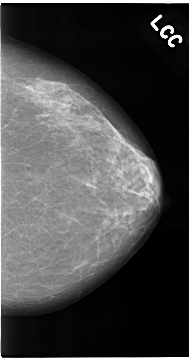

C_0096_1.LEFT_CC

LEFT_CC LINES 4688 PIXELS_PER_LINE 2456 BITS_PER_PIXEL 12 RESOLUTION 50 NON_OVERLAY